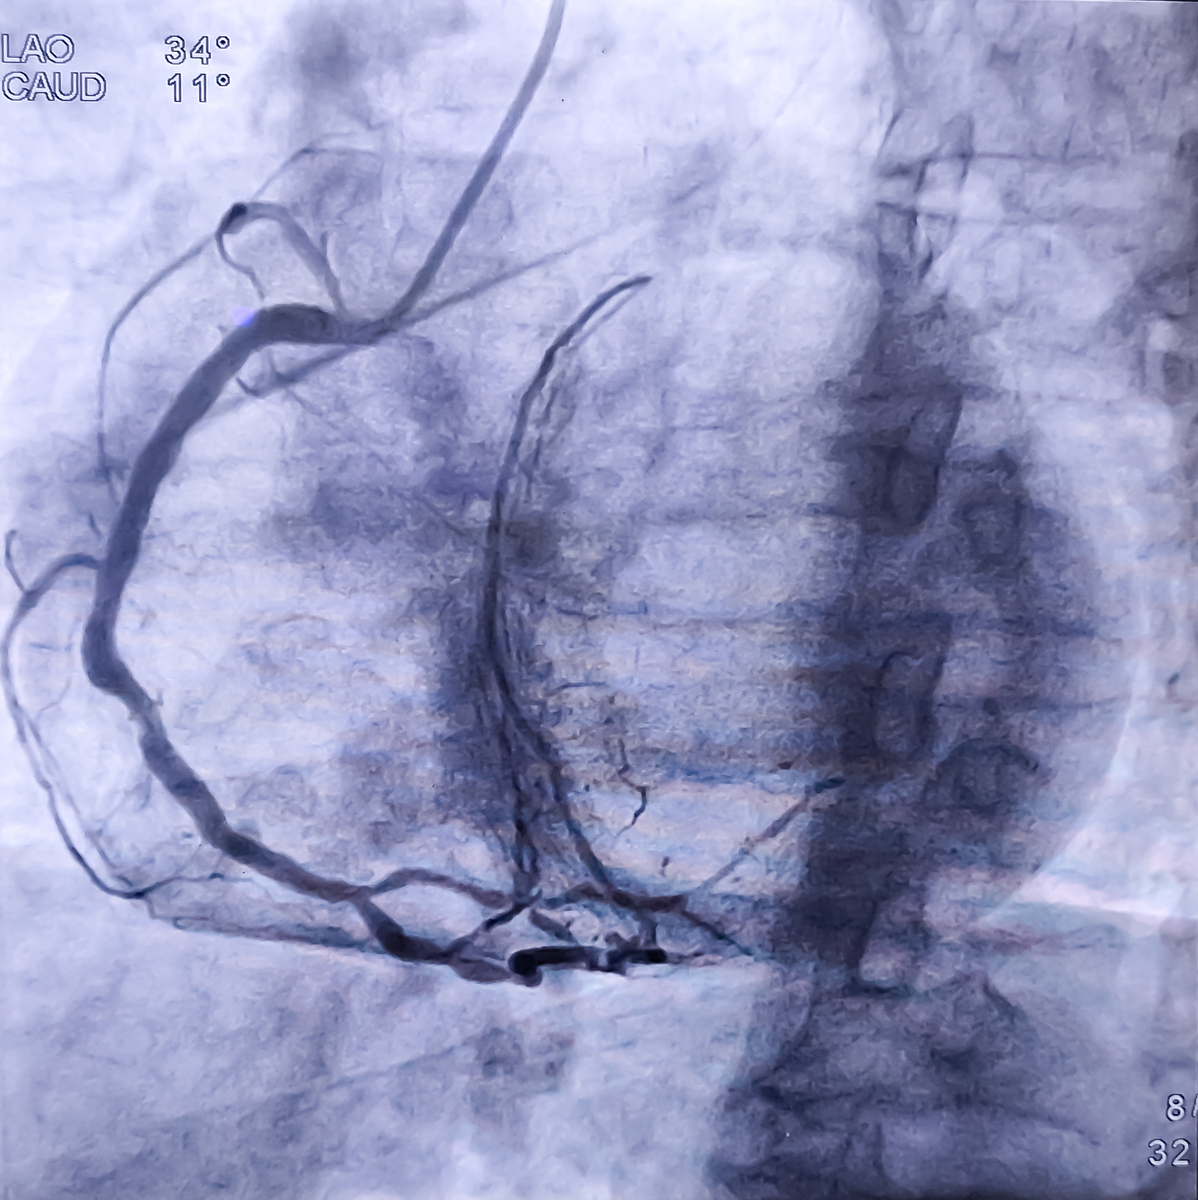

肺动脉造影术和肺动脉扩张术是两种常见的肺动脉介入治疗技术。与国内同类技术相比,它们有以下比较:

总体来说,肺动脉造影术和肺动脉扩张术在国内已经有较高的应用水平,并且随着国内技术的不断发展和完善,与国外的同类技术相比,差距在逐渐缩小。